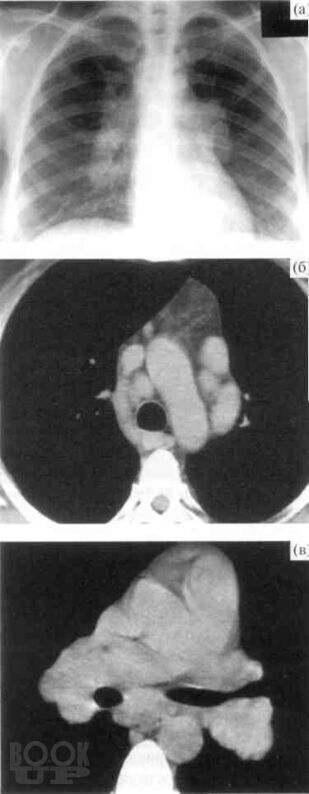

В учебно-методическом пособии авторы представили данные об этиологии, патогенез, патологической анатомии саркоидоза, клинико-рентгенологические классификации, методы диагностики лабораторные, лучевые (рентгенография, томография, КТ, МРТ, ПЭТ), радиоизотопное, бронхологические особенности современного саркоидоза. Приведены примеры собственных наблюдений.